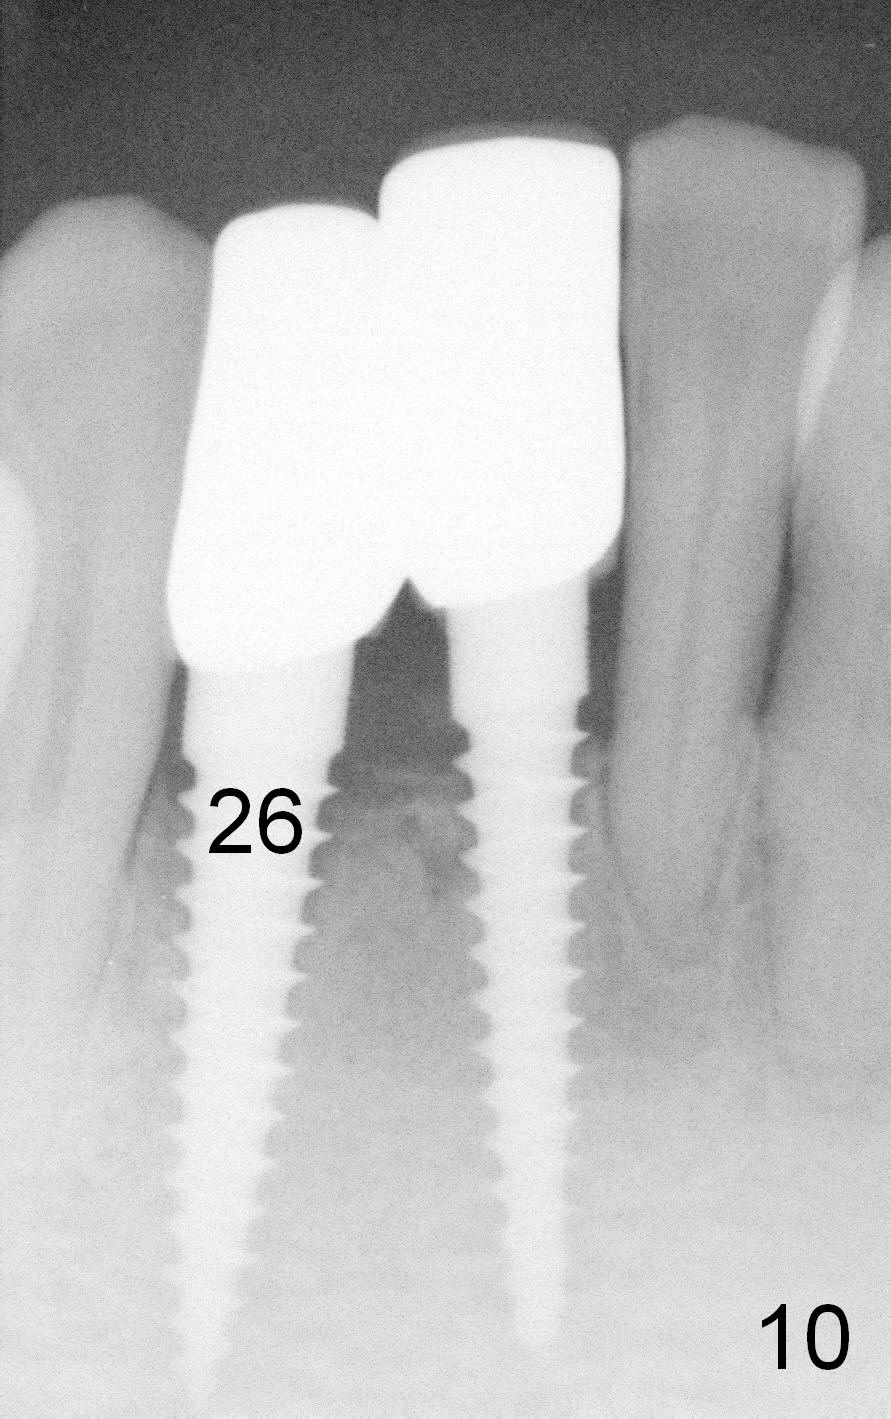

A 60-year-old lady wants to remove 2 mobile lower right incisors (Fig.1,2; with infection at the lateral (>)). Immediate 1-piece implants are placed (Fig.3,4): 3x17 mm at the central, 3.5x17 mm at the lateral. Insertion torque is > 60 Ncm for the implants. No bone graft is placed. After prep (Fig.5), two separate provisionals are fabricated (Fig.6). The one at the lateral incisor looks bulky at the cervix, because of the oversized implant for the site (over-engineering). Use of smaller implant (3.0 (instead of 3.5), 2.5 (instead of 3.0) or 2.0 mm) may solve the problem. Seven days postop, the infection resolves (Fig.7 >) with normal-looking papilla (*).